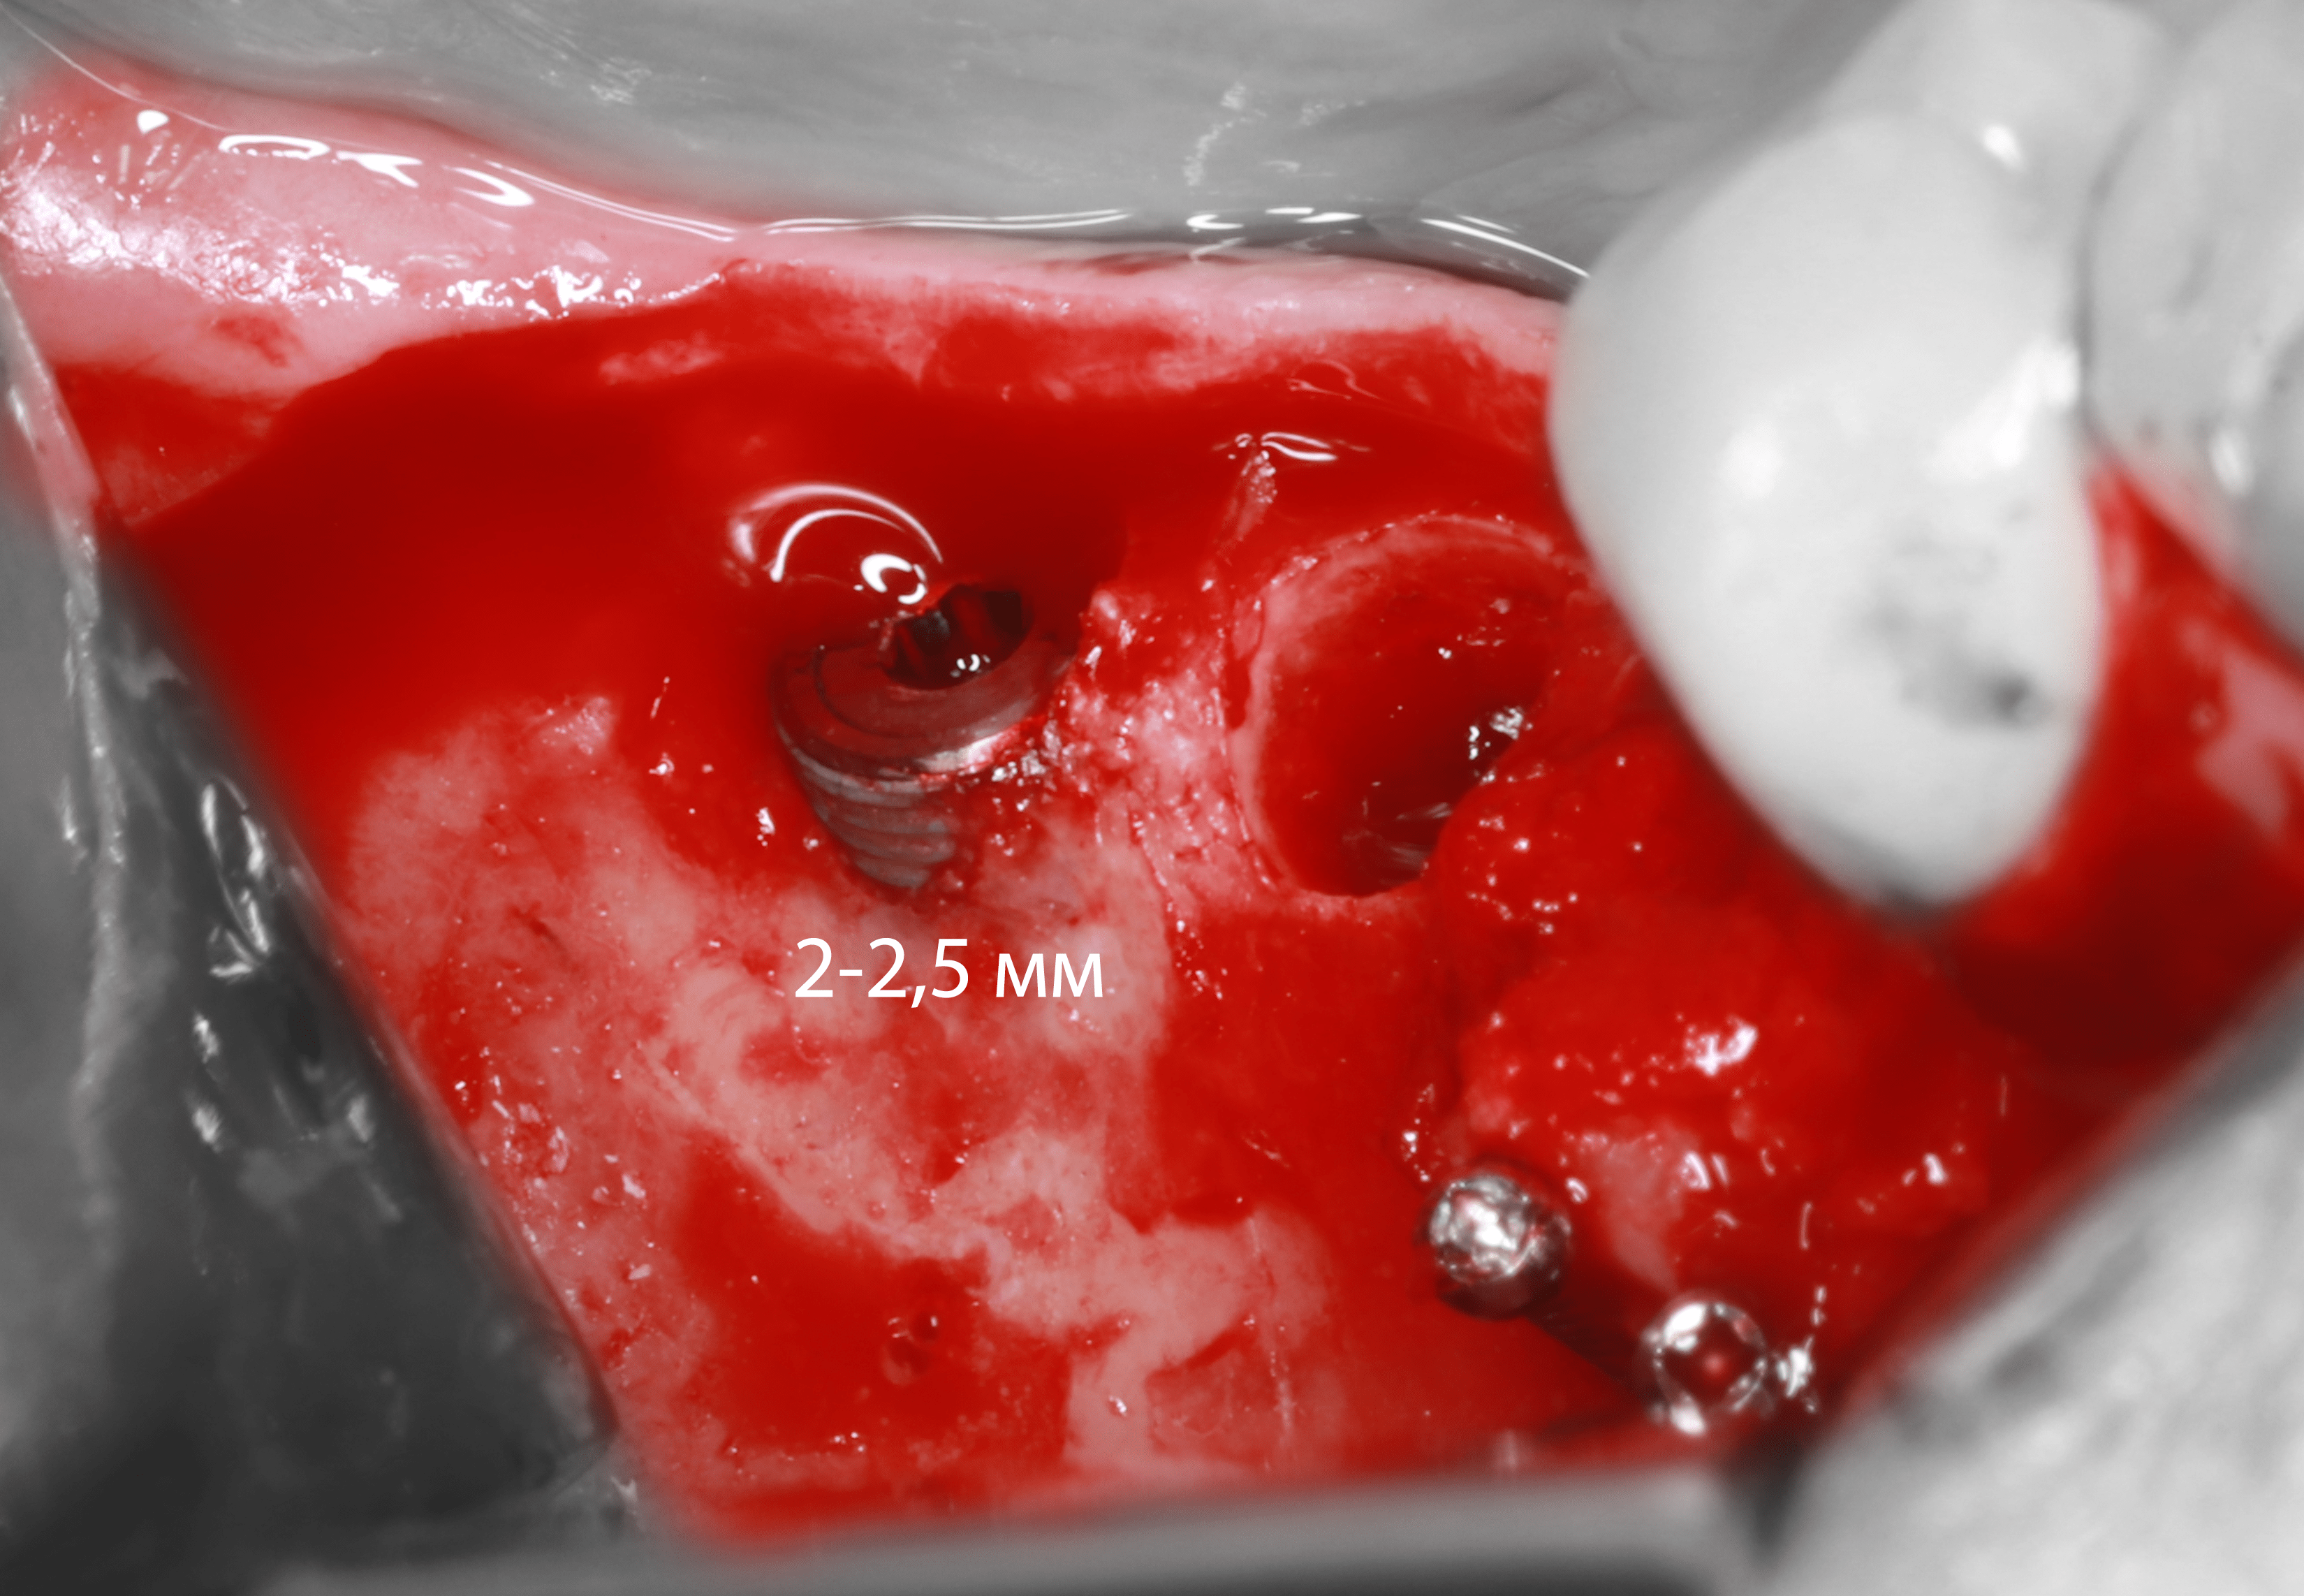

3-4) Проведена остеотомии с помощью трепанов MEISINGER

6) Установлен мезиальный имплантат, фиксирован костный трансплантат с помощью прижатия винтами (1мм.*10мм.)

7) Установлен дистальный имплантат - дегистенция имплантата глубиной 2-2,5 мм.